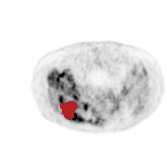

There has been growing research interest in using deep learning based method to achieve fully automated segmentation of lesion in Positron emission tomography computed tomography(PET CT) scans for the prognosis of various cancers. Recent advances in the medical image segmentation shows the nnUNET is feasible for diverse tasks. However, lesion segmentation in the PET images is not straightforward, because lesion and physiological uptake has similar distribution patterns. The Distinction of them requires extra structural information in the CT images. The present paper introduces a nnUNet based method for the lesion segmentation task. The proposed model is designed on the basis of the joint 2D and 3D nnUNET architecture to predict lesions across the whole body. It allows for automated segmentation of potential lesions. We evaluate the proposed method in the context of AutoPet Challenge, which measures the lesion segmentation performance in the metrics of dice score, false-positive volume and false-negative volume.